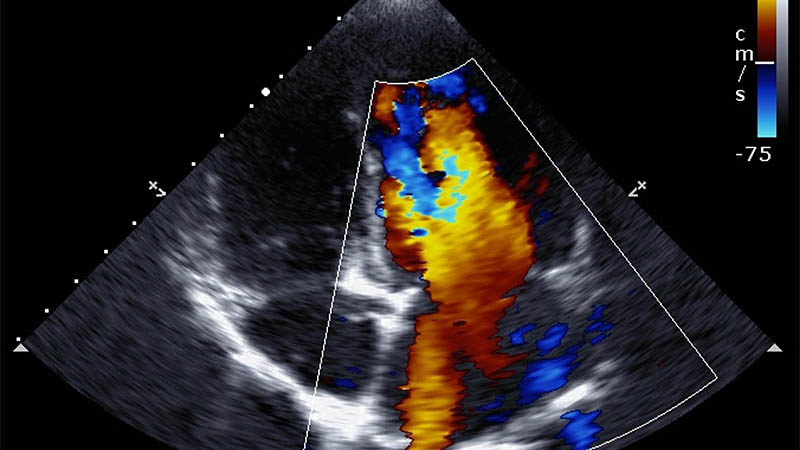

Transesophageal echocardiography in the imaging of spinal cord structures – a systematic review of the literature

Martyna Mendrala, Sylweriusz Kosiński, Tomasz Darocha, Paweł Podsiadło, Tomasz Czober, Konrad Mendrala

J Ultrason 2025; 25: 28